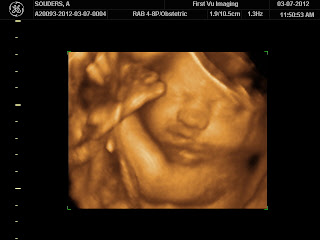

Grammie, Poppa, Brandon, Presley, and I all got to view little Harper on the big screen. It's just as incredible the second time around. However, Miss H did not want to put her hands and feet down. They stayed up by her head almost the entire time, so we didn't get a whole lot of face shots.

The first shot we got of Harper was almost the exact same one we got of Presley. Both had a foot in each hand covering their faces.

Presley was pretty still in each of her shots, so the clarity is a lot better. The ultrasound tech was constantly chasing Harper around in my belly. She noticed that Harper was opening and closing her eyes a lot, and was surprised by how alert she was. I think she might have been on a sugar high because I didn't want her to be sleepy, but I didn't tell the tech that. Alert? Sugar high? Pretty much the same thing, right??? Also, when I was up on the ultrasound table, Presley grabbed my hand and kept telling me, "it's okay, Mommy. Be very still, Mommy." Love my sweet girl.

The ultrasound tech thought Harper looked a lot like her big sister in this shot.

Big yawn

I promise that Harper does not have a black eye here.

Squishy face (that's her foot right next to her eye)

Another face shot